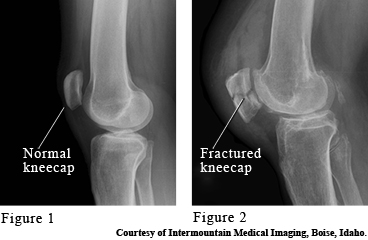

Images of a normal and broken kneecaps

The kneecap (patella) is a bone that protects the front of your knee joint. It takes the brunt of blows to your knee, such as a fall onto a knee or a knee hitting the dashboard. A broken kneecap (fracture) causes swelling and pain, especially when moving the knee back and forth.